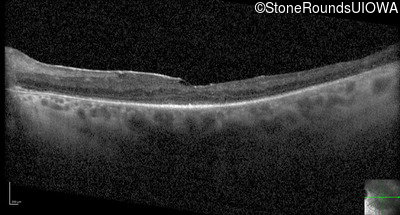

Optical Coherence Tomography - Left - 20/40 -1

Exemplar / OCT Stack

OCT Stack